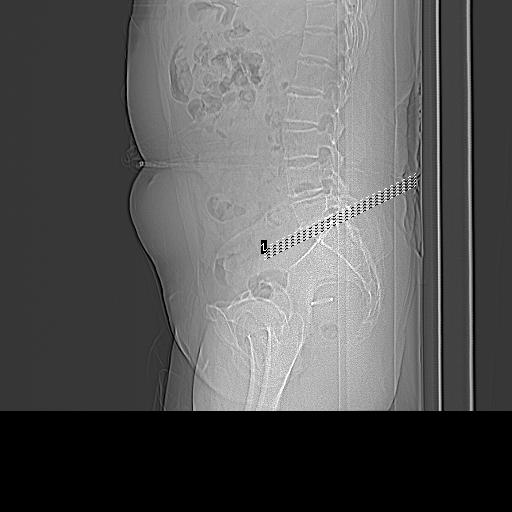

患者;女性;左下肢疼痛。

l5s1显示椎间盘突出,椎体边缘骨质增生,双侧黄韧带钙化。(请上传骨窗)

l4-5椎间隙略窄,应该扫描。

l5s1椎间盘向后脱出使脊膜囊受压,椎体边缘骨质增生,双侧黄韧带钙化。l45椎间盘估计亦突出,为何未扫。